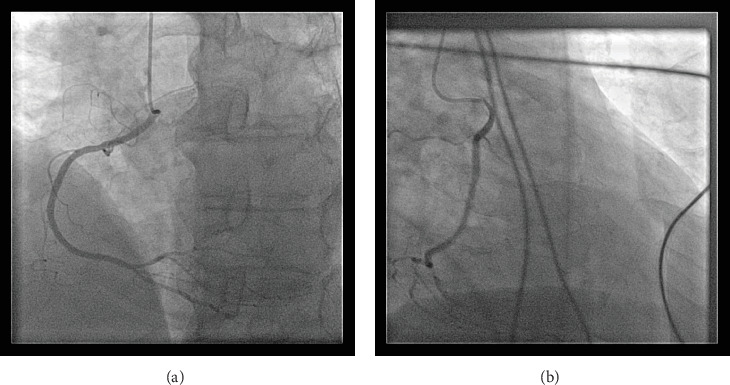

摘要冠状动脉异常起源是一种罕见的先天性心脏缺陷。随着心脏计算机断层扫描和磁共振成像技术的应用,冠状动脉异常的检测可能会增加。一旦发现异常冠状动脉,手术干预的建议取决于患者的症状、应激成像上是否存在诱导性缺血以及高危解剖特征。77岁男性,有高血压、高脂血症、慢性肾脏病III期和中度主动脉狭窄病史,表现为非st段抬高型心肌梗死,横断面成像发现右冠状动脉主动脉起源异常。他的主动脉狭窄也从中度发展到重度,目前尚不清楚他的心肌梗死是否完全归因于主动脉深度狭窄背景下的供需差异,或者他异常的冠状动脉解剖结构是否可能是导致他出现这种情况的罪魁祸首。一个多学科的心脏小组决定进行经导管主动脉瓣置换术,如果他的心绞痛症状在瓣膜置换术后持续存在,然后重新对他的右冠状动脉异常进行手术干预。

Anomalous aortic origin of a coronary artery is a rare congenital heart defect. The detection of anomalous coronary arteries is likely to increase with increased availability and application of cardiac computed tomography and magnetic resonance imaging. Once detected, the recommendation for surgical intervention on anomalous coronary arteries depends upon patient symptoms, the presence or absence of inducible ischemia on stress imaging, and high-risk anatomic features. A 77-year-old man with a history of hypertension, hyperlipidemia, chronic kidney disease Stage III, and moderate aortic stenosis presented with a non-ST-elevation myocardial infarction and was found to have an anomalous aortic origin of the right coronary artery on cross-sectional imaging. His aortic stenosis had also progressed from moderate to severe, and it was not clear whether his myocardial infarction could be exclusively attributed to a supply-demand disparity within the context of profound aortic stenosis or if his aberrant coronary anatomy could be implicated as the culprit for his presentation. A multidisciplinary heart team decided to proceed with a transcatheter aortic valve replacement and then readdress surgical intervention on his anomalous right coronary artery if his anginal symptoms persisted following valve replacement.